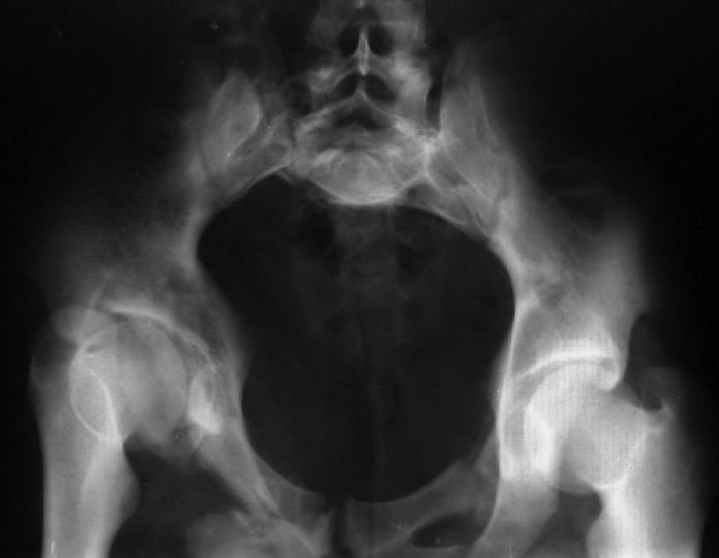

Re: Застарелый перелом таза

Уважаемый Юрий Алексеевич, обсудить показания к оперативному лечению возможно после выяснения полной клинической картины (боль, опороспособность, ходьба, сидение, половая функция, неврологический статус), данные кт и косых проекций.

Для информации к размышлению о возможности исправления имеющейся деформации предлагаю похожий случай.